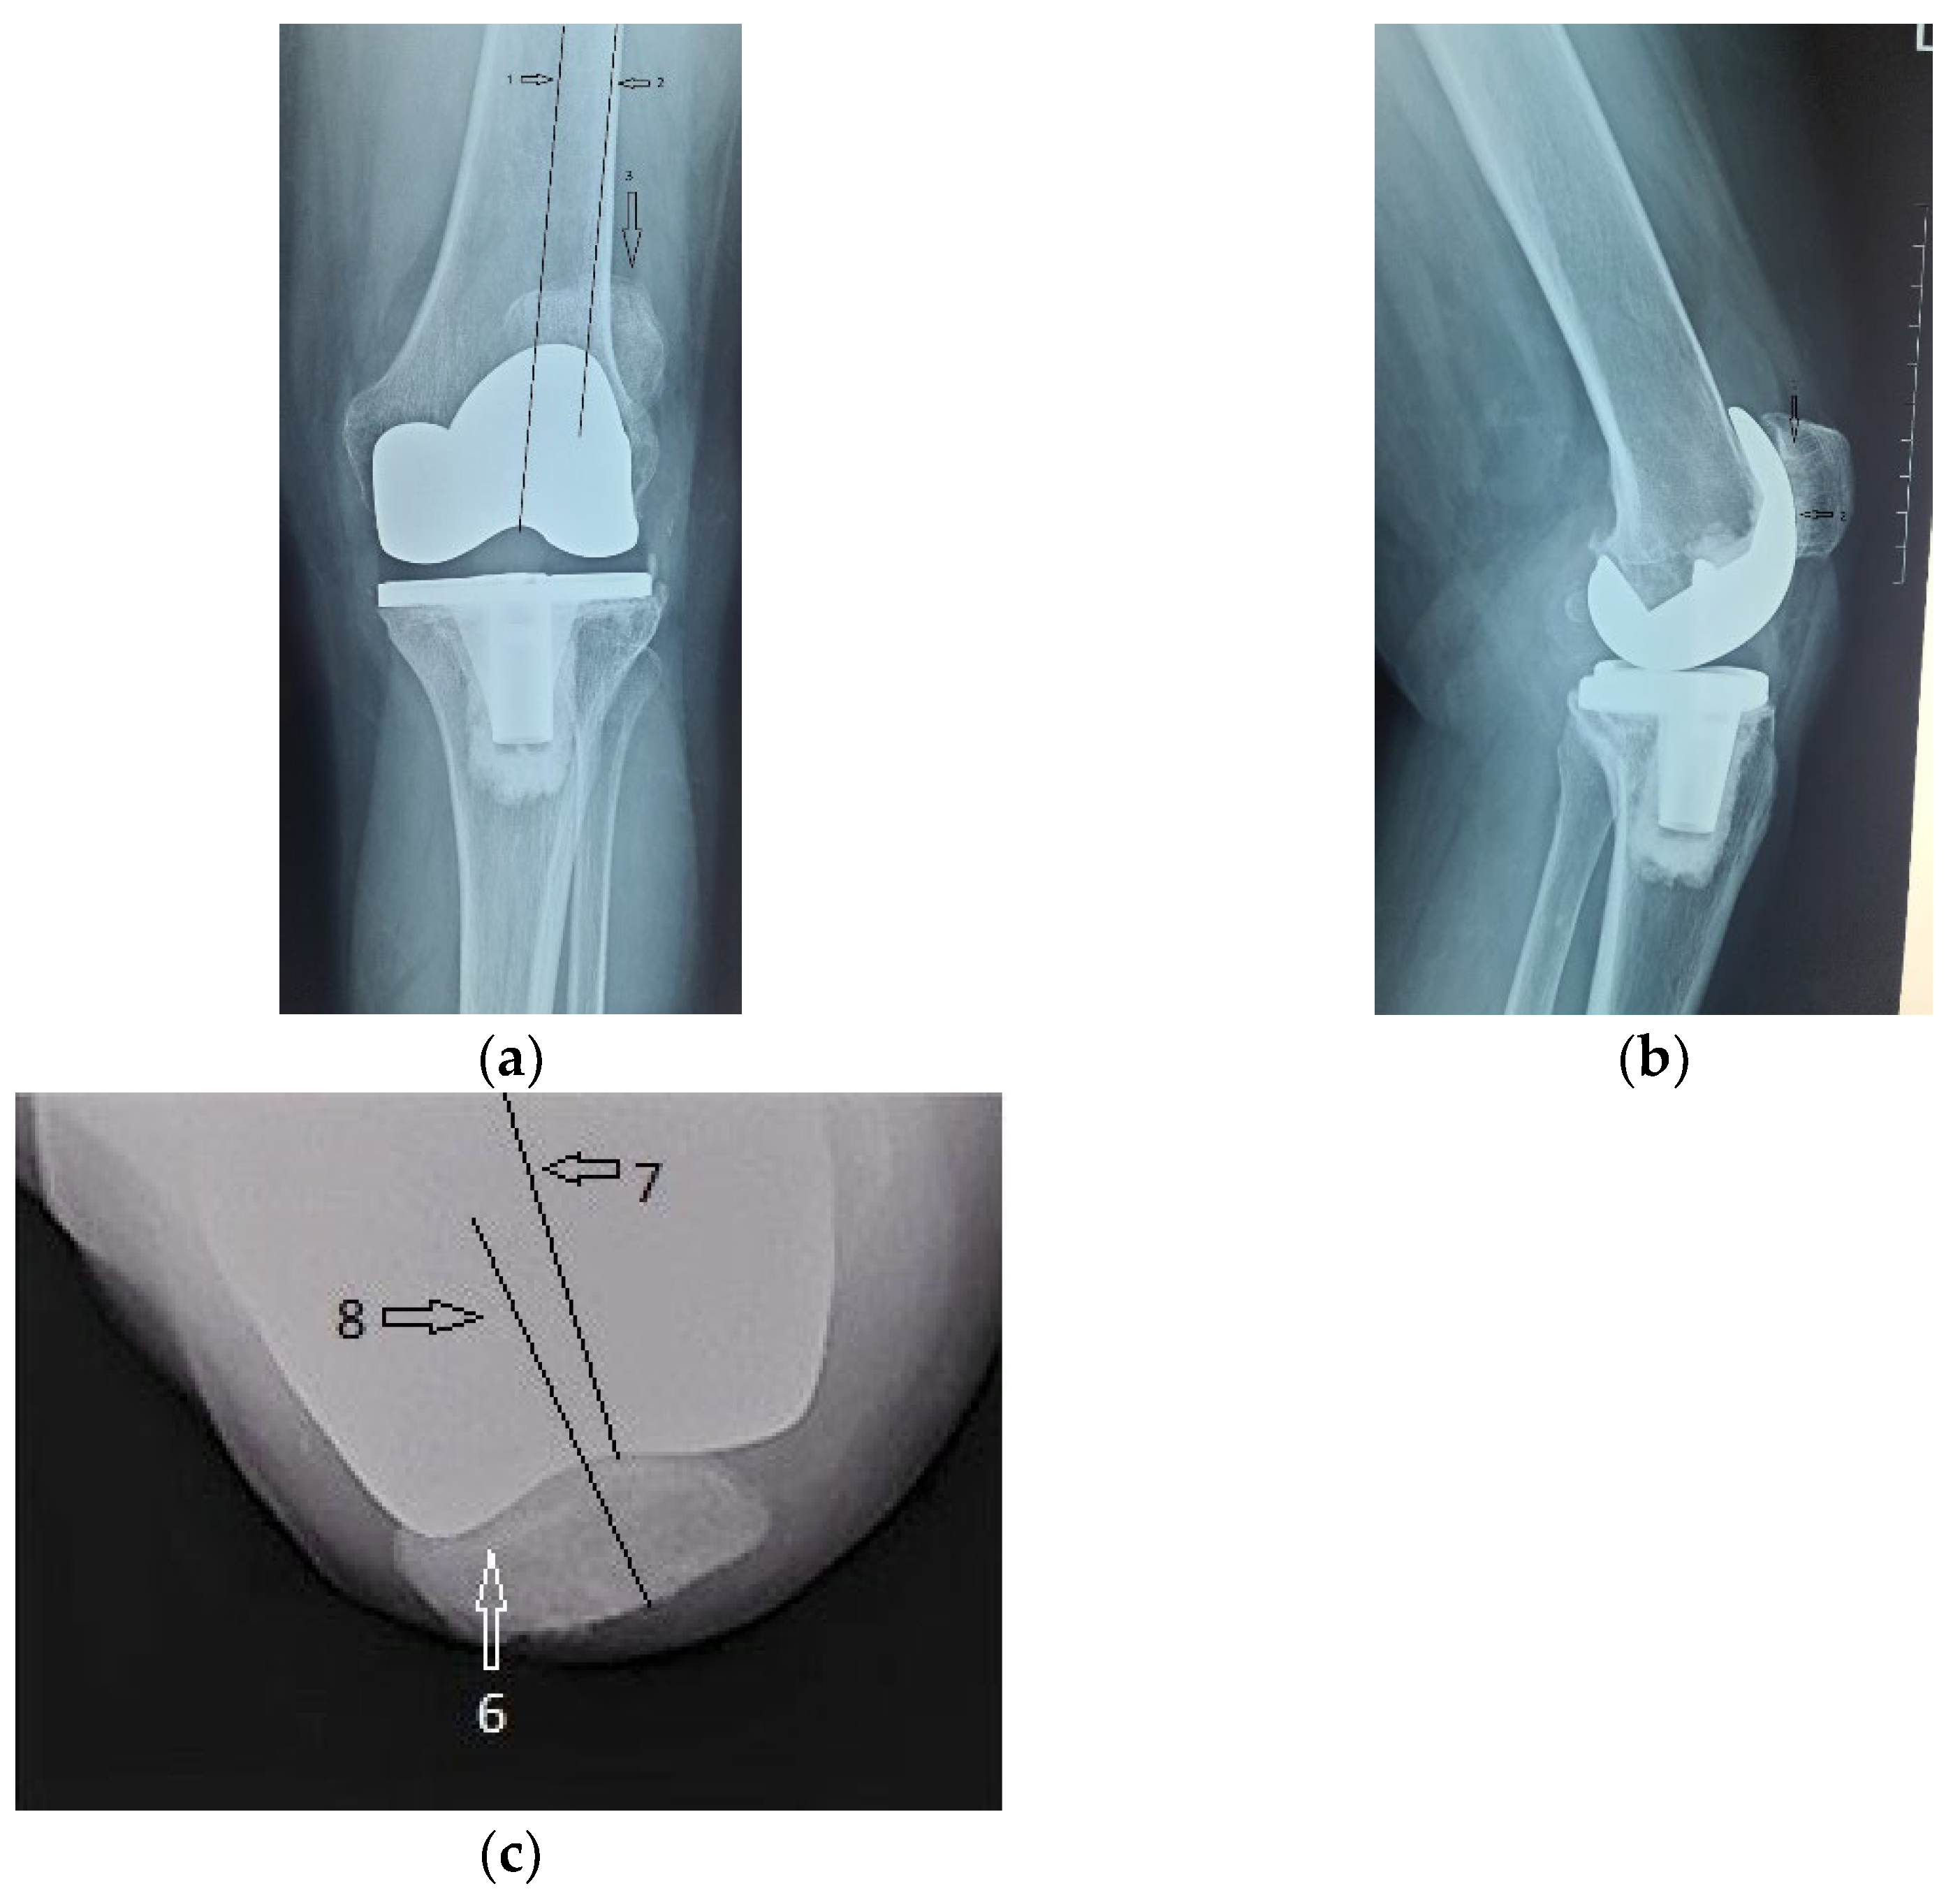

Alongside with the clinical scores, the patient was also evaluated radiologically, with CT scans and standard X-rays. Radiological investigations, using coronal, lateral and axial views (Merchant view) showed patellar arthrosis and a slight lateral subluxation of the patella (Figure 4).

Figure 4.

(a) coronal view, patellar lateral subluxation (arrow) compared to femoral axis with (1) marking the femoral trochlear axis, (2) patellar axis and (3) the patella must be centered in the femoral trochlea; (b) lateral view, patellar wear, patellar trochlea deformation and subchondral bone condensation with (4) marking subchondral osteocondensation and (5) patella bone deformation; (c) axial view, patellar lateral subluxation, and deformation, osteocondesation of the subchondral bone with (6) patella bone deformation and condensation, (7) femoral trochlear axis and (8) Patellar axis.